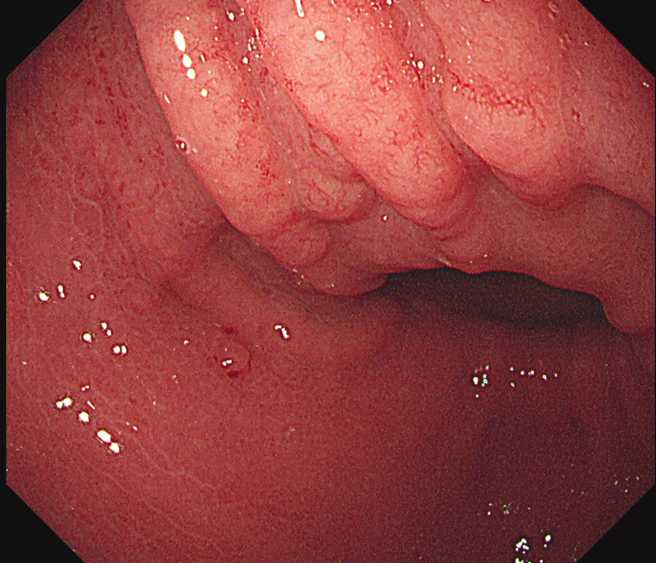

禾馨民权健康管理诊所院长林相宏8日在脸书粉专分享,曾有一名30岁的女性来诊所做健康检查,虽然照胃镜时并没有发现肿瘤,但他发现对方胃壁上有许多类似「苦瓜表面」的小结节突起,怀疑是胃幽门螺旋杆菌感染。

医师林相宏替病患照胃镜,发现胃壁表面有如「苦瓜表面」的小结节突起。(图/翻摄自脸书粉专胰臟医师林相宏)